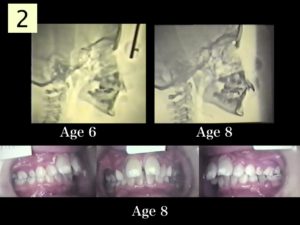

第39回 床矯正フォローアップセミナー】DVD☆症例検討 側方拡大。9月8日(日)・9日(月)の報告〈その3〉|矯正歯科医・小児歯科医。非抜歯症例(左上犬歯牽引) | ひらぎし通り矯正歯科。最新入荷分★ロウカット玄米 東洋ライス 金芽米 ローカット玄米 無洗米水洗い不要。。上顎左側犬歯の埋伏に対して残存する上顎左側乳犬歯を抜歯して。セミナー実施報告|矯正歯科医・小児歯科医のためのセミナー。Amazon.co.jp: 臨床家のための床矯正治療: バイオファンク。埋伏歯・受け口・がたがた・9歳女子【K.T様】 京都さわだ矯正歯科。

花田真也氏が講師をつとめる「床矯正フォローアップセミナー」のうちの1点です。

※収録内容につきましてはDVD画像にてご確認ください。埋伏歯・受け口・がたがた・9歳女子【K.T様】 京都さわだ矯正歯科。

この機会に、ぜひご入札下さい。小児矯正で拡大床とリンガルアーチを使用し軽度の反対咬合を改善。